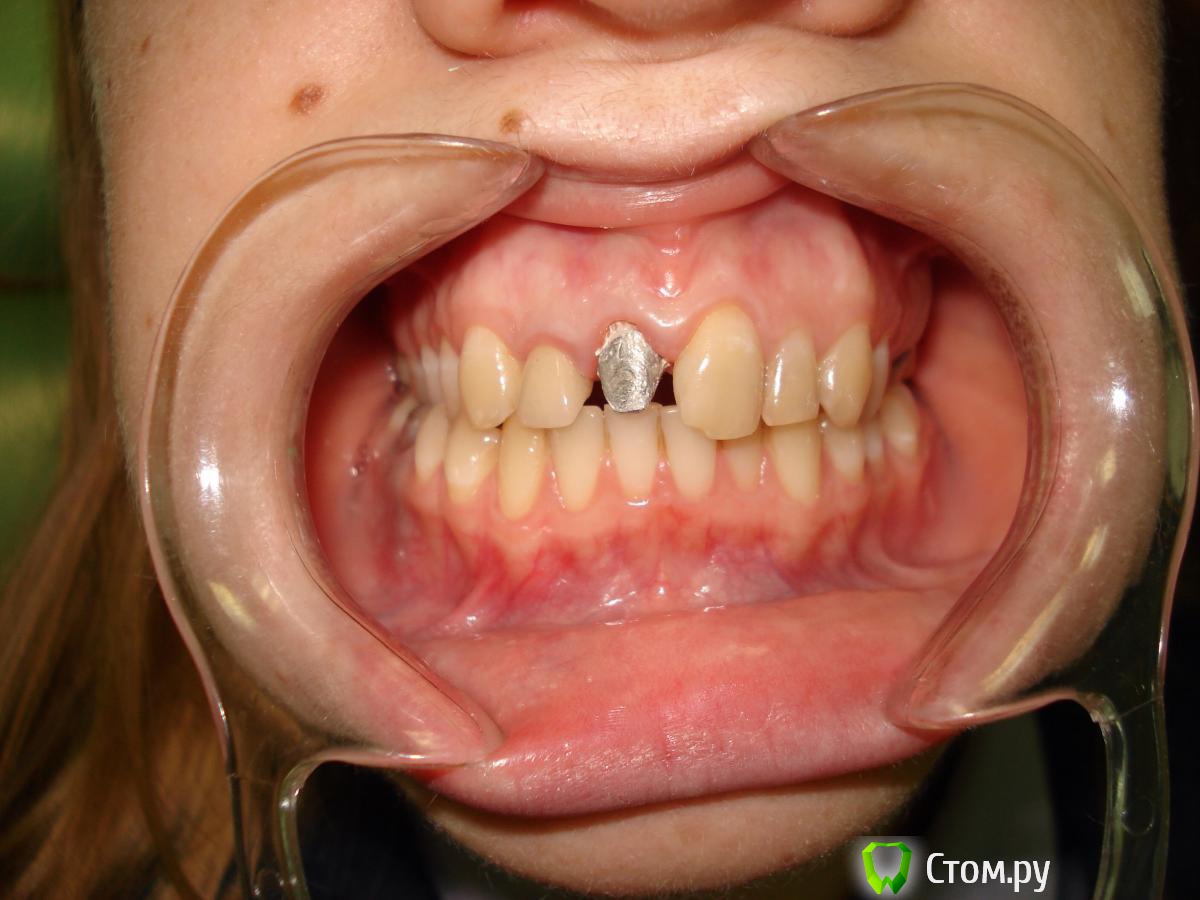

StomDoc Опубликовано 26 ноября, 2013 Поделиться Опубликовано 26 ноября, 2013 Пациентка обратилась с жалобой на скол 11 зуба, доктор поставил метал вкладку но уступа практически нет так же как и на 12 где м/к коронка и вкладка планирую поднять зениты на 11 и 12 зубах тем самым получить хоть какой то минимальный феррул. Какое ваше мнение? И если ставить циркон на передние зубы нужно можно ли их поставить на метал вкладку?? Ссылка на комментарий